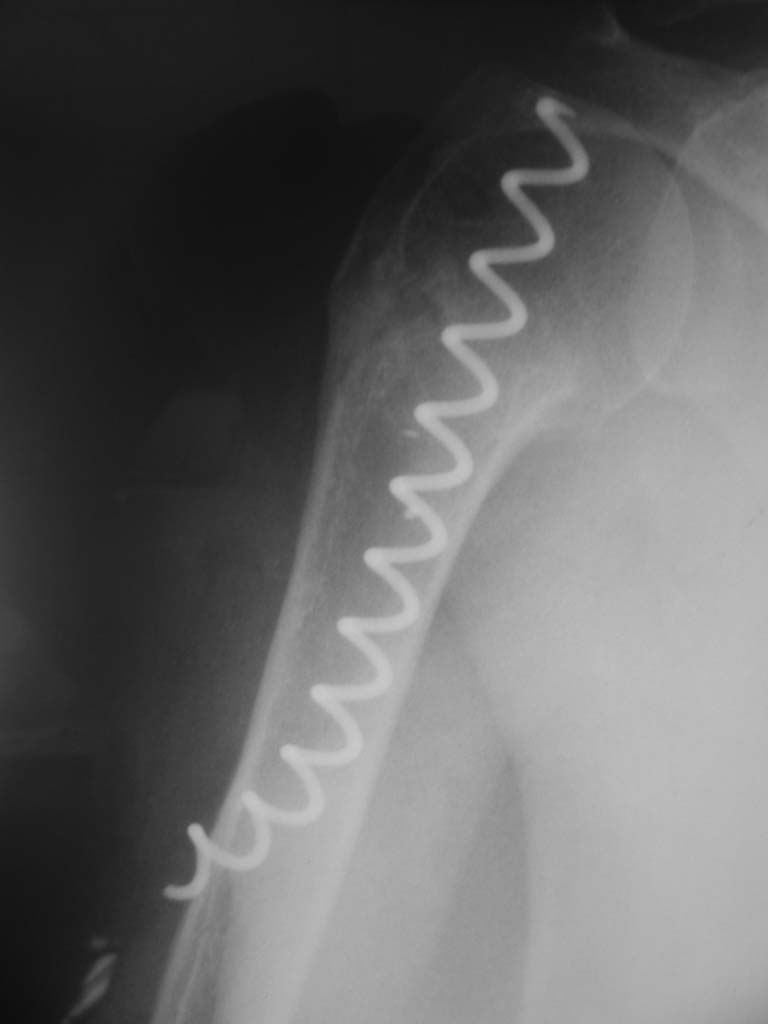

Здравствуйте Евгений. В используемых Вами методиках остеосинтеза переломов хирургической шейки плечевой кости имеются ряд недостатков. Метод Лазарева хорош, как малоинвазивное вмешательство, но автор умалчивает о таких осложнениях как миграция спиц. Консолидация перелома начинается с резорбции костной ткани в месте перелома, в связи с этим спицы выходя за пределы субхондрального слоя головки плеча, и мигрируют в полость сустава, обеспечивая импиджмент синдром. Накостные фиксаторы (какие бы они не были) чаще используются для открытого остеосинтеза, что неизбежно ведёт к нарушению кровообращея в головке, далее к элементам асептического некроза с вытекающими последствиями. Обратите внимание метод спирального остеосинтеза, который по философии отвечает принципам остеосинтеза при низкой минеральной плостности кости. Эту методику я внедрил 2 года назад, и опна себя оправдывает. Статью по этому поводу Вы можете найте в сборнике съезда травматологов России, которых был в Саратове. (см фото) С Уважением, Комков Андрей.